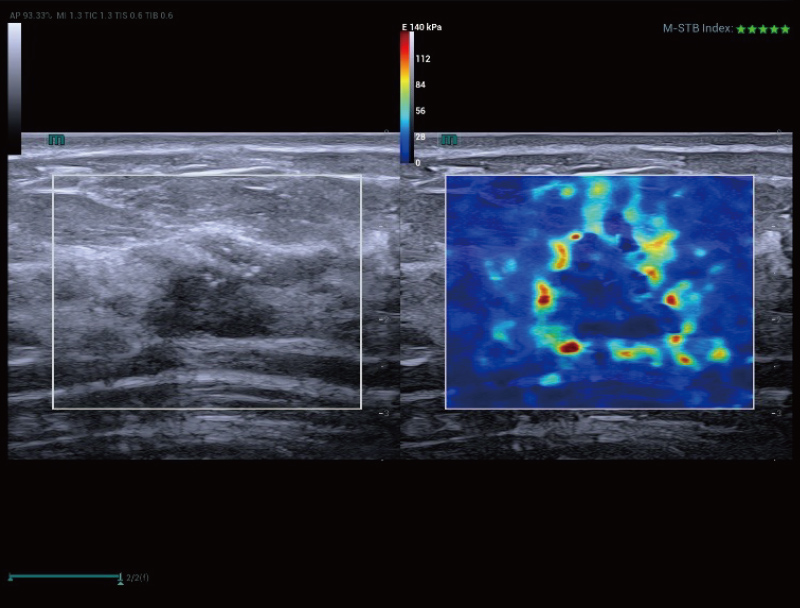

STVi consente la valutazione quantitativa della viscosit├Ā dei tessuti e fornisce immagini multiparametriche in tempo reale, offrendo un approccio pi├╣ completo alla diagnosi per immagini e all'analisi quantitativa di malattie epatiche croniche, lesioni mammarie e altre condizioni.

Valutazione del tumore al seno